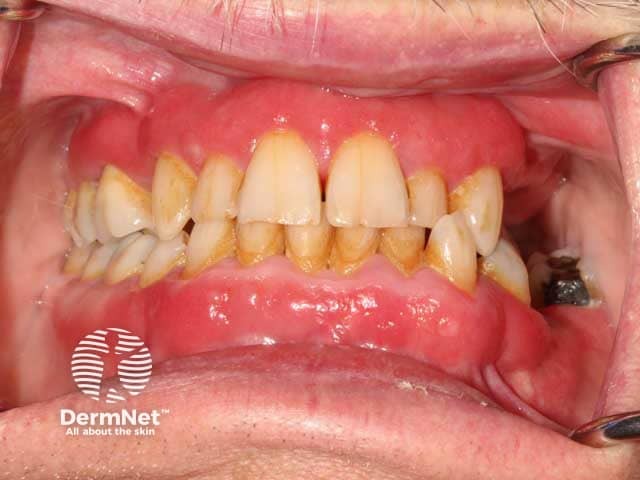

Red, glazed and oedematous changes on the gingivae in plasma cell mucositis (PCM-patient1)

Red, glazed and oedematous changes on the gingiva and buccal mucosa in plasma cell mucositis (PCM-patient1)

Plasma cell mucositis most commonly affects the oral mucosa and gingiva. Although it is typically painful with potential oral and oropharyngeal functional consequences, it can also be asymptomatic.